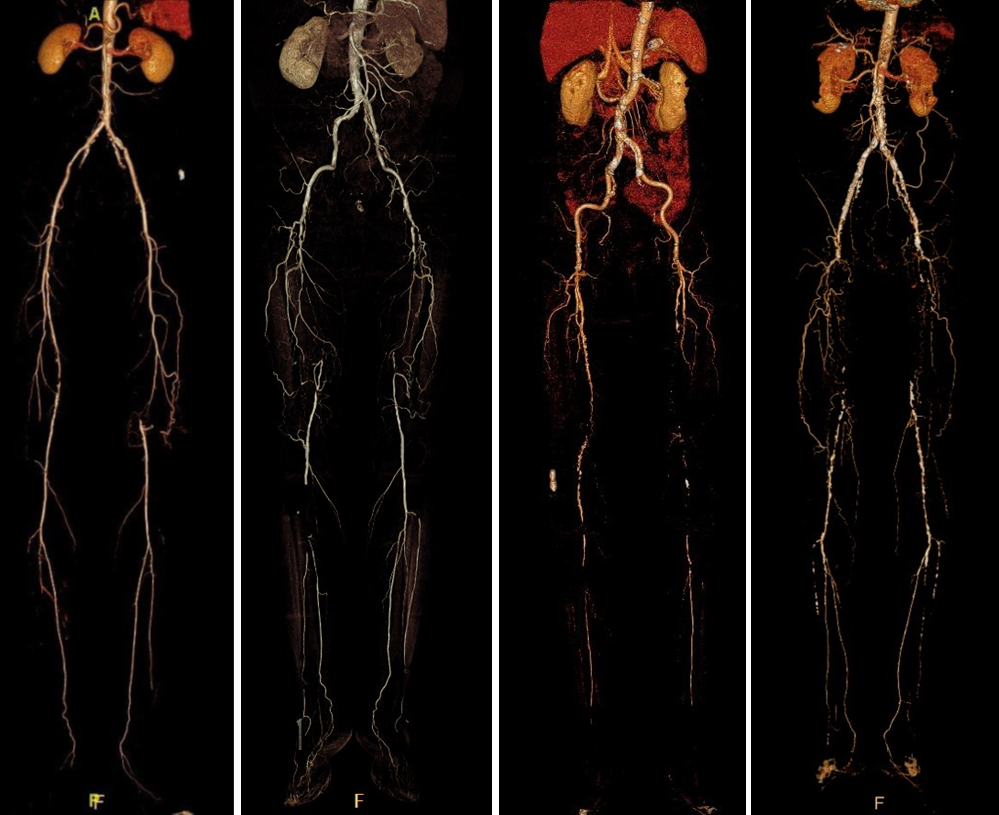

★ Case 1

noproximal stump in SFA,>250mm

★ Case 2

significantdistal collaterals